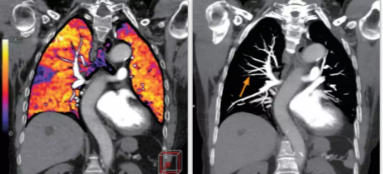

肺智能柔性減影成像功能發(fā)現(xiàn)亞段肺栓塞

相比傳統(tǒng)成像方式,肺部柔性減影技術(shù)通過人工智能,對(duì)平掃數(shù)據(jù)和CT肺動(dòng)脈血管掃描數(shù)據(jù)進(jìn)行智能比對(duì),解碼并識(shí)別各個(gè)器官(肺、氣管、肺動(dòng)脈、肺靜脈、主動(dòng)脈等)的空間位置,并在三維空間中進(jìn)行體素級(jí)的柔性配準(zhǔn),從而極大提升了不同序列數(shù)據(jù)的空間位置的一致性。通過肺部柔性減影技術(shù)可得到肺強(qiáng)化碘圖,可以顯示出傳統(tǒng)CTPA圖像看不到的小栓塞病變,提高了栓塞檢出率,其結(jié)果甚至可與SPECT吻合。